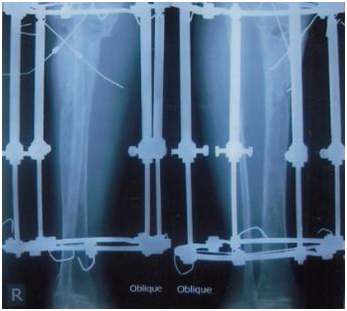

Figure 7 2 rings (above and below) with 4 telescopic rods applied for segmental transportation by 2 olive wires.

Figure 8 Radiographic view after 3 months follow up.